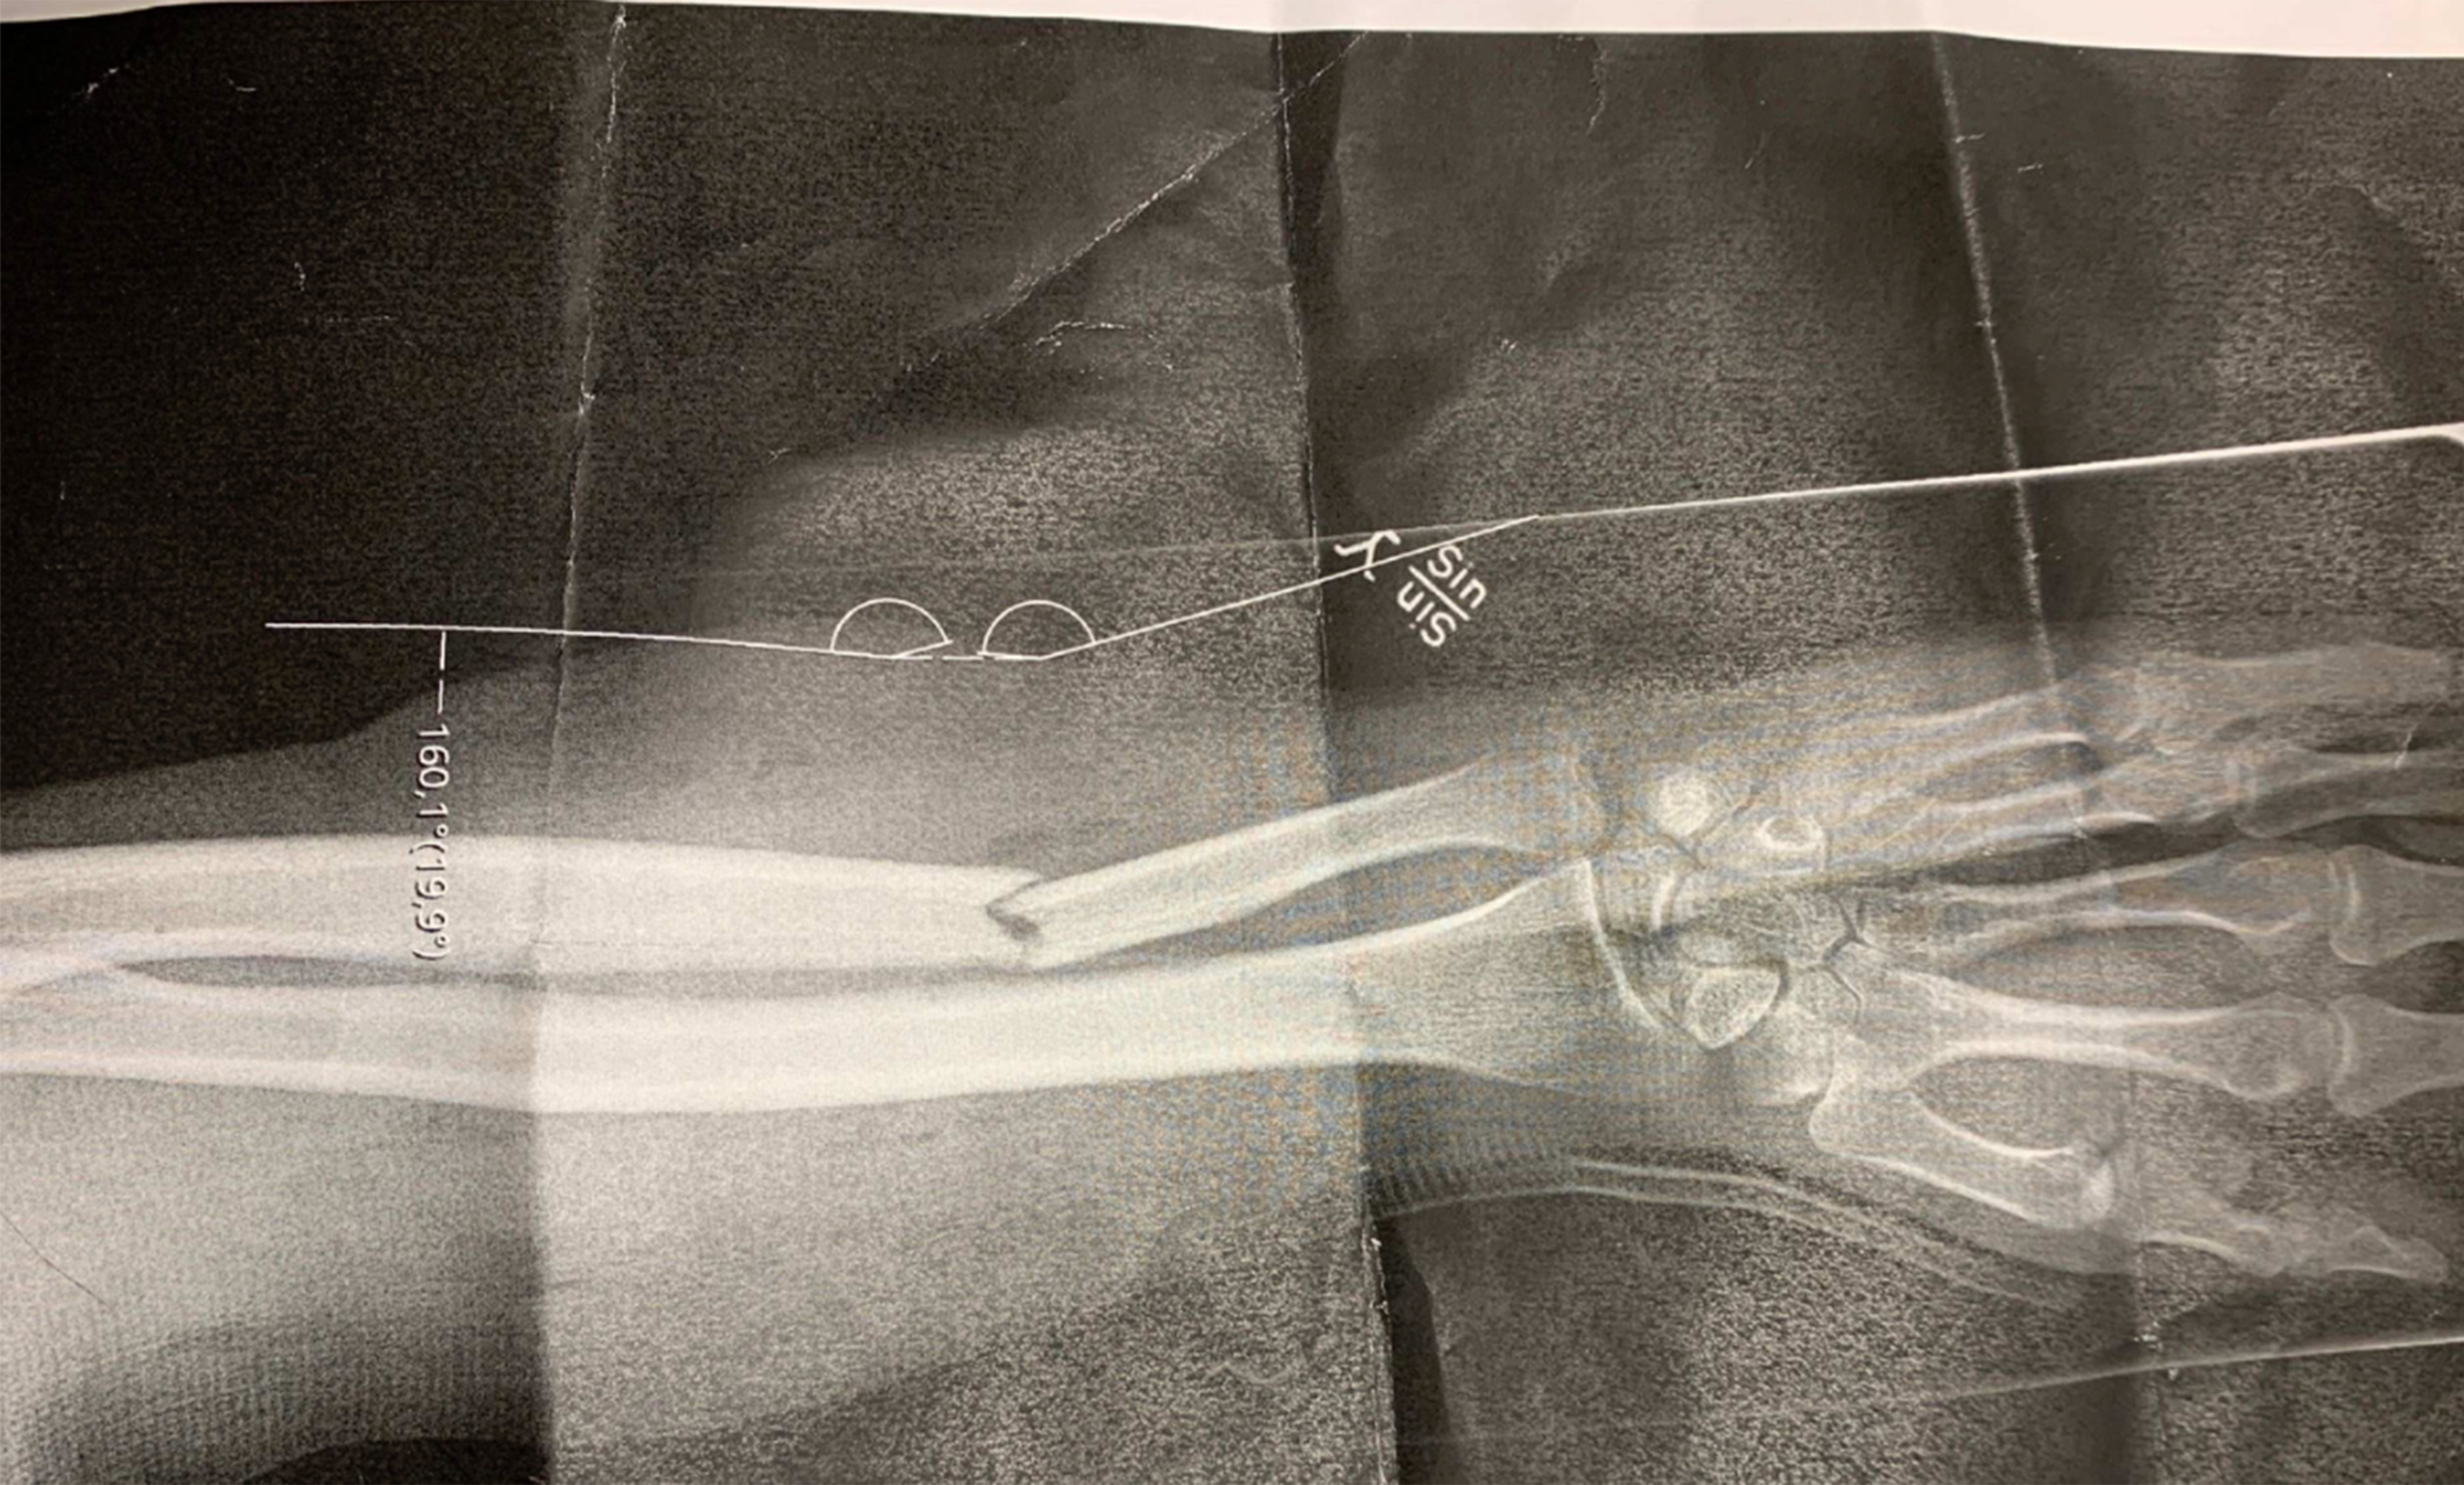

Röntgenbild på 35-åringens brutna arm.

35-åringen åker ambulans. På sjukhuset konstateras att han brutit armen och han opereras för sina skador.